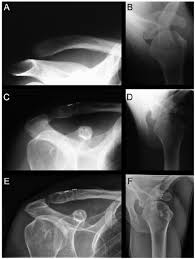

Distal Clavicle Fractures Trauma Orthobullets

Distal Clavicle Fractures Trauma Orthobullets from upload.orthobullets.com